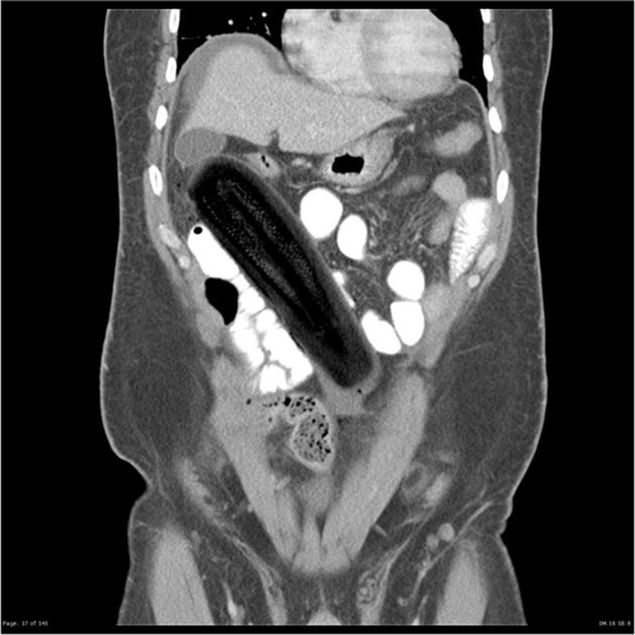

Un alt caz uluitor a avut loc in 1979 si i-a socat pe medici in momentul in care le-a spus ca a stat timpde 6 luni cu un vibrator in zona rectala.

Lista rusinoasa a radiografiilor inedite este completata de imagini cu o vanata, o jucarie de plastic, un deodorant sau chiar un telefon mobil! Toate aflate "captive" in aceeasi zona a corpului.